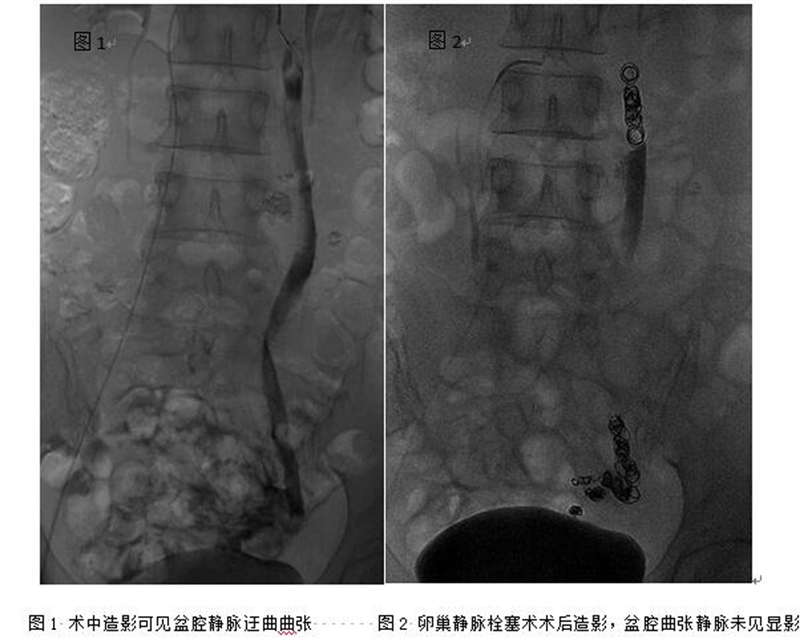

??? 在與徐女士充分溝通后,陸煒決定用導(dǎo)管靜脈栓塞術(shù)來幫助徐女士解除病痛。手術(shù)進(jìn)展很順利,術(shù)后,徐女士下腹部疼痛癥狀明顯好轉(zhuǎn),目前已康復(fù)出院。據(jù)悉,這是全市首例完成的導(dǎo)管靜脈栓塞術(shù)治療盆腔淤血綜合征。

??? CT檢查提示,徐女士盆腔內(nèi)靜脈曲張,左卵巢靜脈擴(kuò)張嚴(yán)重。市人民醫(yī)院血管外科主任陸煒綜合評(píng)估了徐女士的情況,診斷她患有一種盆腔隱匿疾病---盆腔淤血綜合征。